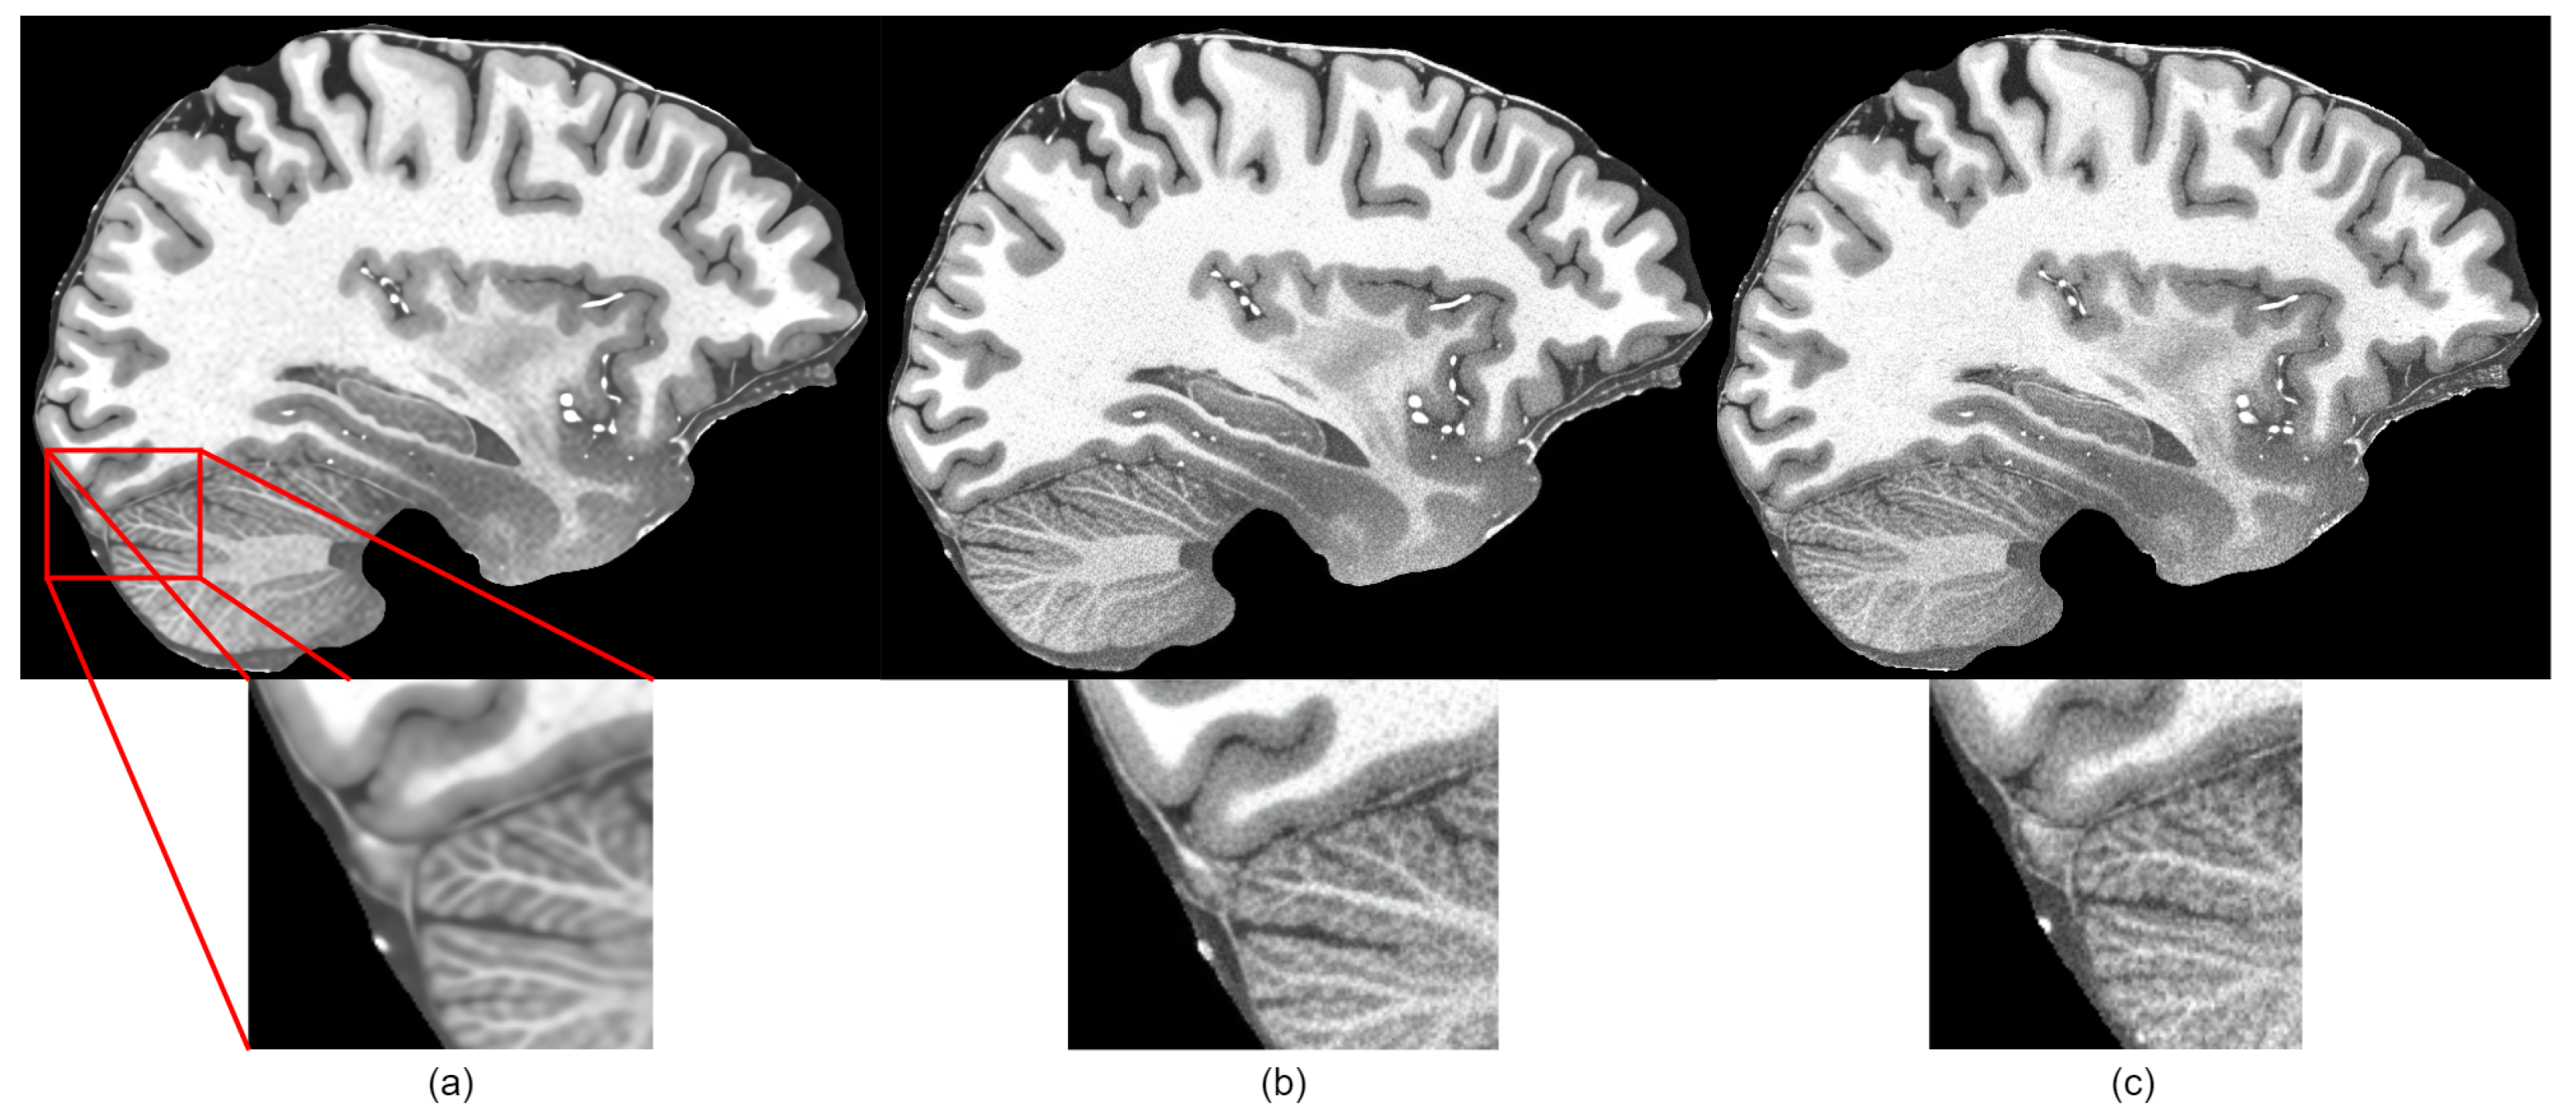

4.3. Results

4.4. Discussion